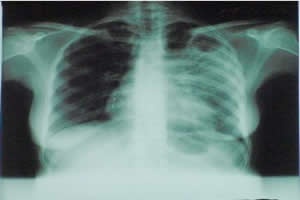

(Foto Divulgação/Ilustrativa)

São Bento – No último dia 24 foi lembrado o Dia Mundial de Combate à Tuberculose. Em São Bento do Sul, nos últimos quatro anos foram registrados quarenta e oito casos de pacientes com a doença. A Secretaria de Saúde conta com uma equipe responsável pelo programa, oferecendo aos pacientes atendimento no Centro de Vigilância à Saúde e medicamentos gratuitamente. Segundo o médico Rodinei Garcia, coordenador do programa, é importante que as notificações dos casos sejam repassadas para os profissionais. “Assim, poderemos atuar imediatamente e fazer o controle de todas as pessoas próximas ao paciente, evitando desta forma a proliferação do bacilo”, ressaltou o médico. Em 2010, foram dezoito casos registrados (com dois abandonos, um óbito e uma transferência). No ano seguinte foram 15 quinze casos (um abandono, um óbito e uma transferência). Em 2012, doze casos (com um abandono). Agora em 2013, são três casos (com uma transferência).